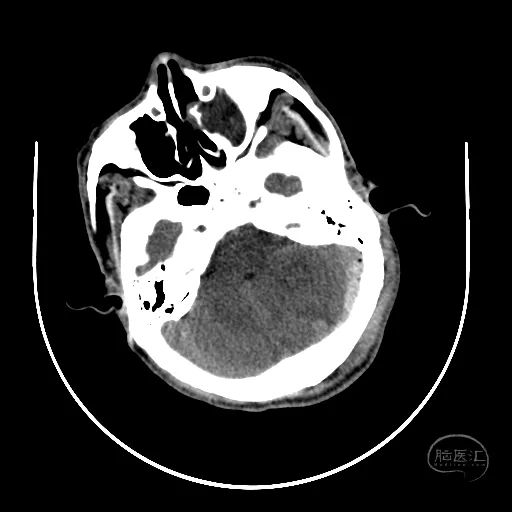

术后第一天复查CT显示后颅窝血肿清除,第四脑室隐约可见。

患者昏迷状,GCS评分3分,双侧瞳孔等大等圆,直径3mm,对光反射迟钝。

额叶血肿清除后,水肿明显。

额叶残余少量血肿,脑室引流管在位。

骨窗见枕骨大孔开放。术中清理枕骨大孔骨折时,无明显出血。